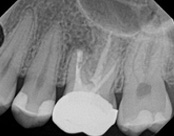

This person had root canal therapy many years ago. One root had excess material outside of the root preventing healing. Another root had a perforation (a hole) and a crack. The large root had a post and had not healed from the initial root canal treatment.

The post was removed, that root was retreated. The root with the excess material, an apicoectomy was done, the excess material, and infection cleaned out. The root with the perforation and crack was removed. The tooth healed and is still in function. This area is a poor area for an implant.